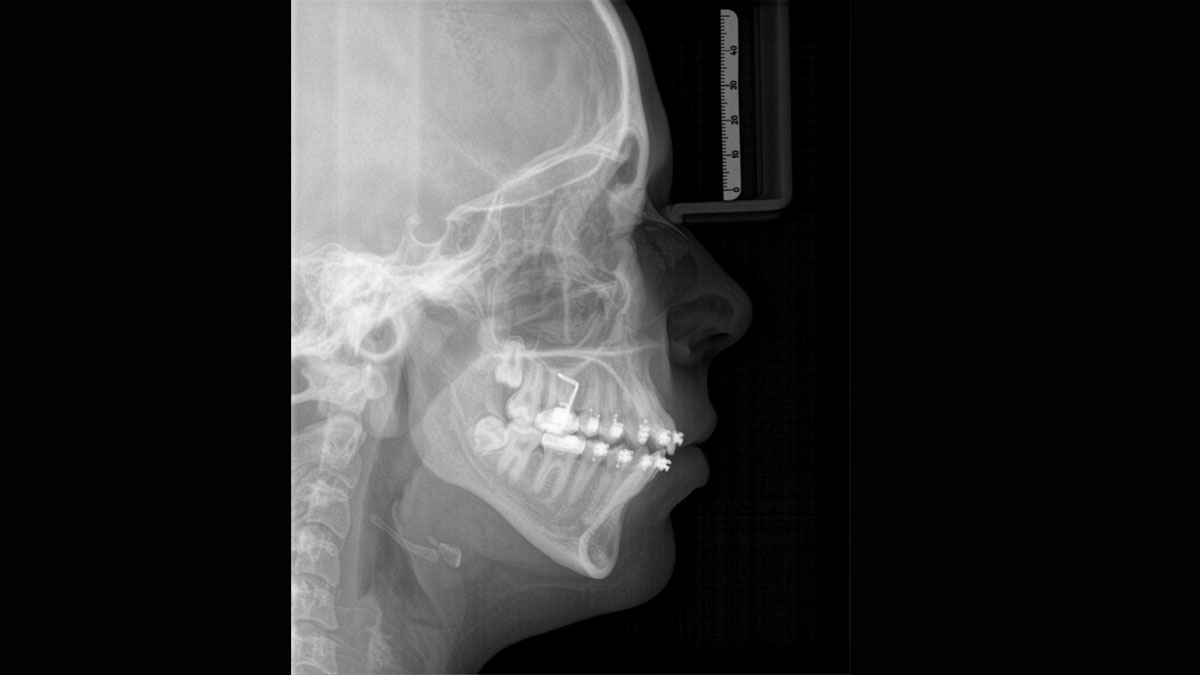

Para obtener imágenes panorámicas excepcionales con alta nitidez. Puede elegir un brazo cefalométrico derecho o izquierdo opcional, que puede reacondicionarse en cualquier momento